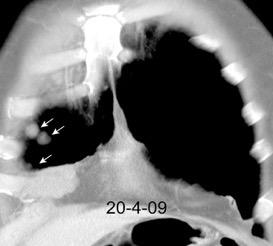

Marzo 2014: Perforación longitudinal distal secundaria a episodio de vómito (síndrome de Boerhaave). Derrame pleural izdo. que evoluciona a empiema.

Wang C-T et al. Tension hydropneumothorax in a Boerhaave syndrome patient: A case report . World J Emerg Med, 2021. Katabathina V et al. Nonvascular, nontraumatic mediastinal emergencies in adults:a comprehensive review of imaging findings. Radiographics. 2011.